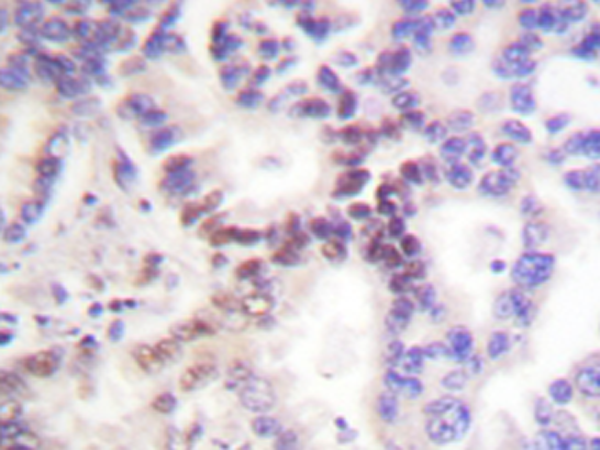

IHC positive control: |

Human lung carcinoma tissue |

IHC Recommend dilution: |

50-100 |